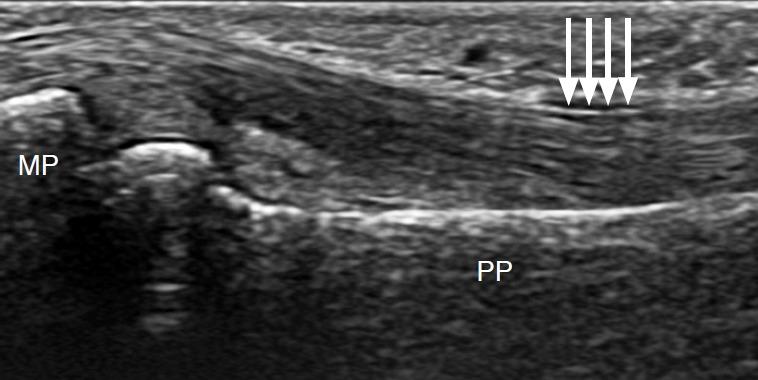

The recent development of advanced high-resolution transducers has enabled the fast, easy, and dynamic ultrasonographic evaluation of small, superficial structures such as the finger. In order to best exploit these advances, it is important to understand the normal anatomy and the basic pathologies of the finger, as exemplified by the following conditions involving the dorsal, volar, and lateral sections of the finger: sagittal band injuries, mallet finger, and Boutonnière deformity (dorsal aspect); flexor tendon tears, trigger finger, and volar plate injuries (volar aspect); gamekeeper's thumb (Stener lesions) and other collateral ligament tears (lateral aspect); and other lesions. This review provides a basis for understanding the ultrasonography of the finger and will therefore be useful for radiologists.

先进的高分辨率换能器的最新发展使得对手指等小而浅表结构进行快速、简便和动态的超声评估成为可能。为了充分利用这些进展,了解手指的正常解剖结构和基本病变非常重要,以下列举了累及手指背侧、掌侧和侧方的一些情况,包括:矢状带损伤、锤状指和纽扣畸形(背侧);屈肌腱撕裂、扳机指和掌板损伤(掌侧);守猎者拇指(斯滕纳损伤)和其他侧副韧带撕裂(外侧);以及其他病变。这篇综述为理解手指的超声检查提供了基础,因此对放射科医生非常有用。